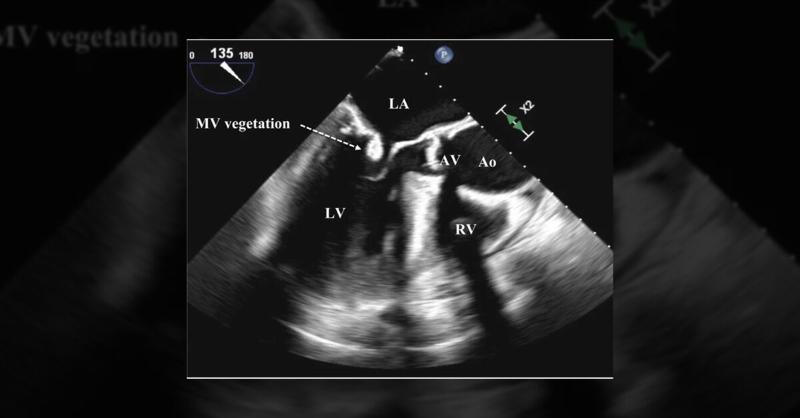

Management of Mitral Valve Endocarditis by T. pyogenes

A 71-year-old man presented experiencing three days of weakness, malaise, and fever following his first dose of Libtayo for recurring basal cell carcinoma. He had an existing history of pancreatic neuroendocrine tumor with liver metastasis and cardiac amyloidosis. On examination, he presented with fever, low blood pressure, increased heart and resp